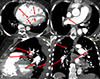

Written informed consent for publication was obtained from a patient. Patient B., a 51-year-old woman with a known history of CTEPH and thrombophilia due to protein C deficiency, was referred to our tertiary cardiac surgery center for further management. On admission, the pulse oximetry was 94% on room air. Echocardiography showed significant right ventricle (RV) systolic dysfunction with fractional area change (FAC) of 22%, end-diastolic right ventricle volume of 106 mL, tricuspid annular plane systolic excursion (TAPSE) of 1.1 cm, with moderate tricuspid regurgitation. Computer tomography (CT) pulmonary angiography confirmed a proximal form of CTEPH (Figure 1). Right heart catheterization showed a pulmonary artery pressure (PAP) 97/45/62 mmHg and the pulmonary vascular resistance (PVR) of 888 dynes/s/cm−5.

Figure 1 CT-angiogram: 1 – axial view shows right atrium (a) and right ventricle (c) enlargement compare to left atrium (b) and left ventricle (d); 2 – sagittal view shows organized thrombi in lobar and segmental branches of left pulmonary artery (red arrows); 3 – axial view shows proximal organized thrombus in right main pulmonary artery (red arrow); 4 – coronal view shows organized thrombi in right and left lobar pulmonary artery branches (red arrows). |